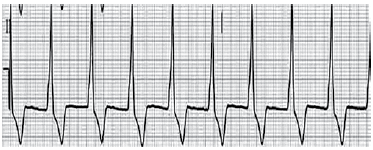

Homem de 57 anos é internado na unidade de terapia intensiva em virtude de dor anginosa iniciada há 12 horas. Logo em seguida, o monitor mostra o traçado a seguir e o paciente sofre uma parada cardiorrespiratória.

A conduta imediata correta inclui: